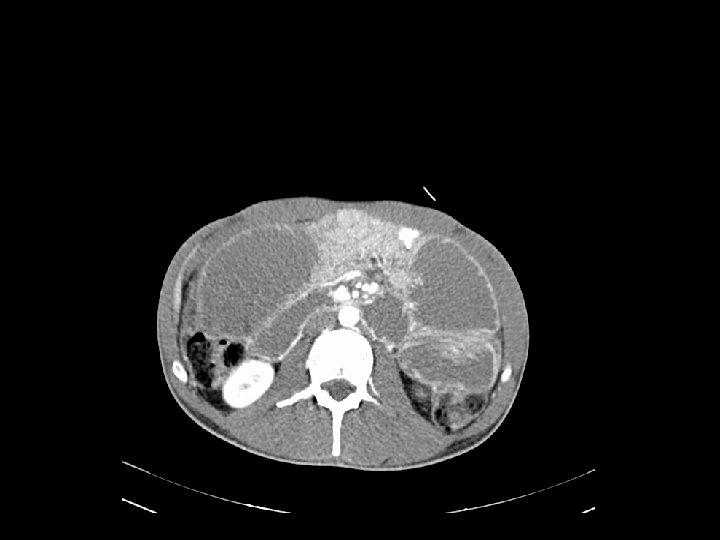

Caso Clínico 1 Laparotomía exploradora (22/08/13) INFORME ANATOMOPATOLÓGICO PIEZA QUIRÚRGICA granyeyuno: dilataciónadenocarcinoma retrógada de asas de yeyuno, duodenodiferenciado, y gástrica con -Hallazgos: Pieza de moderadamente cambio de calibre brusco a nivel de tumoracio n yeyunal. Gran cantidad de ulcerado, que infiltra la totalidad del espesor de la muscular propia, adenopati as en la raiz del meso, mayores de un cm, de consistencia pétrea. Resto de rebasandola, y alcanzando focalmente peritoneo. Cambios inflamatorios cavidad sin hallazgos. Hi gado sin LOES. mixtos inespeci fico, asociados. Bordes de reseccio n sin hallazgos relevantes. RESECCIÓN SEGMENTARIA DE YEYUNO - Ganglios linfa ticos(25): meta stasisde adenocarcinoma (5). Linfadenitis Te cnica: Resección segmentaria de yeyuno de unos 20 cm englobando la tumoracio n en restantes. 2 la ganglios aislados separado: conlos GIA 20 60. Seccio n a nivel- de raiz del meso con mu por ltiples adenopati alinfadenitis s. Diseccio n y exe resis de las adenopati as de mayor taman o que no iban incluidas en la pieza. reactiva.

Caso Clínico 1 Paciente varo n de 24 an os sin antecedentes de intere s, diagnosticado de adenocarcinoma de yeyuno, G 2 p. T 4 N 1 M 0, estadio III En curso actualmente de quimioterapia adyuvante esquema XELOX (hasta la fecha 3 ciclos)